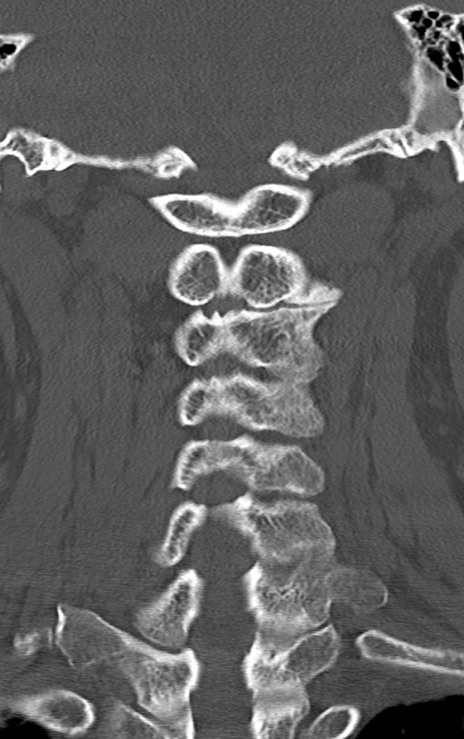

頚椎CT

矢状断像